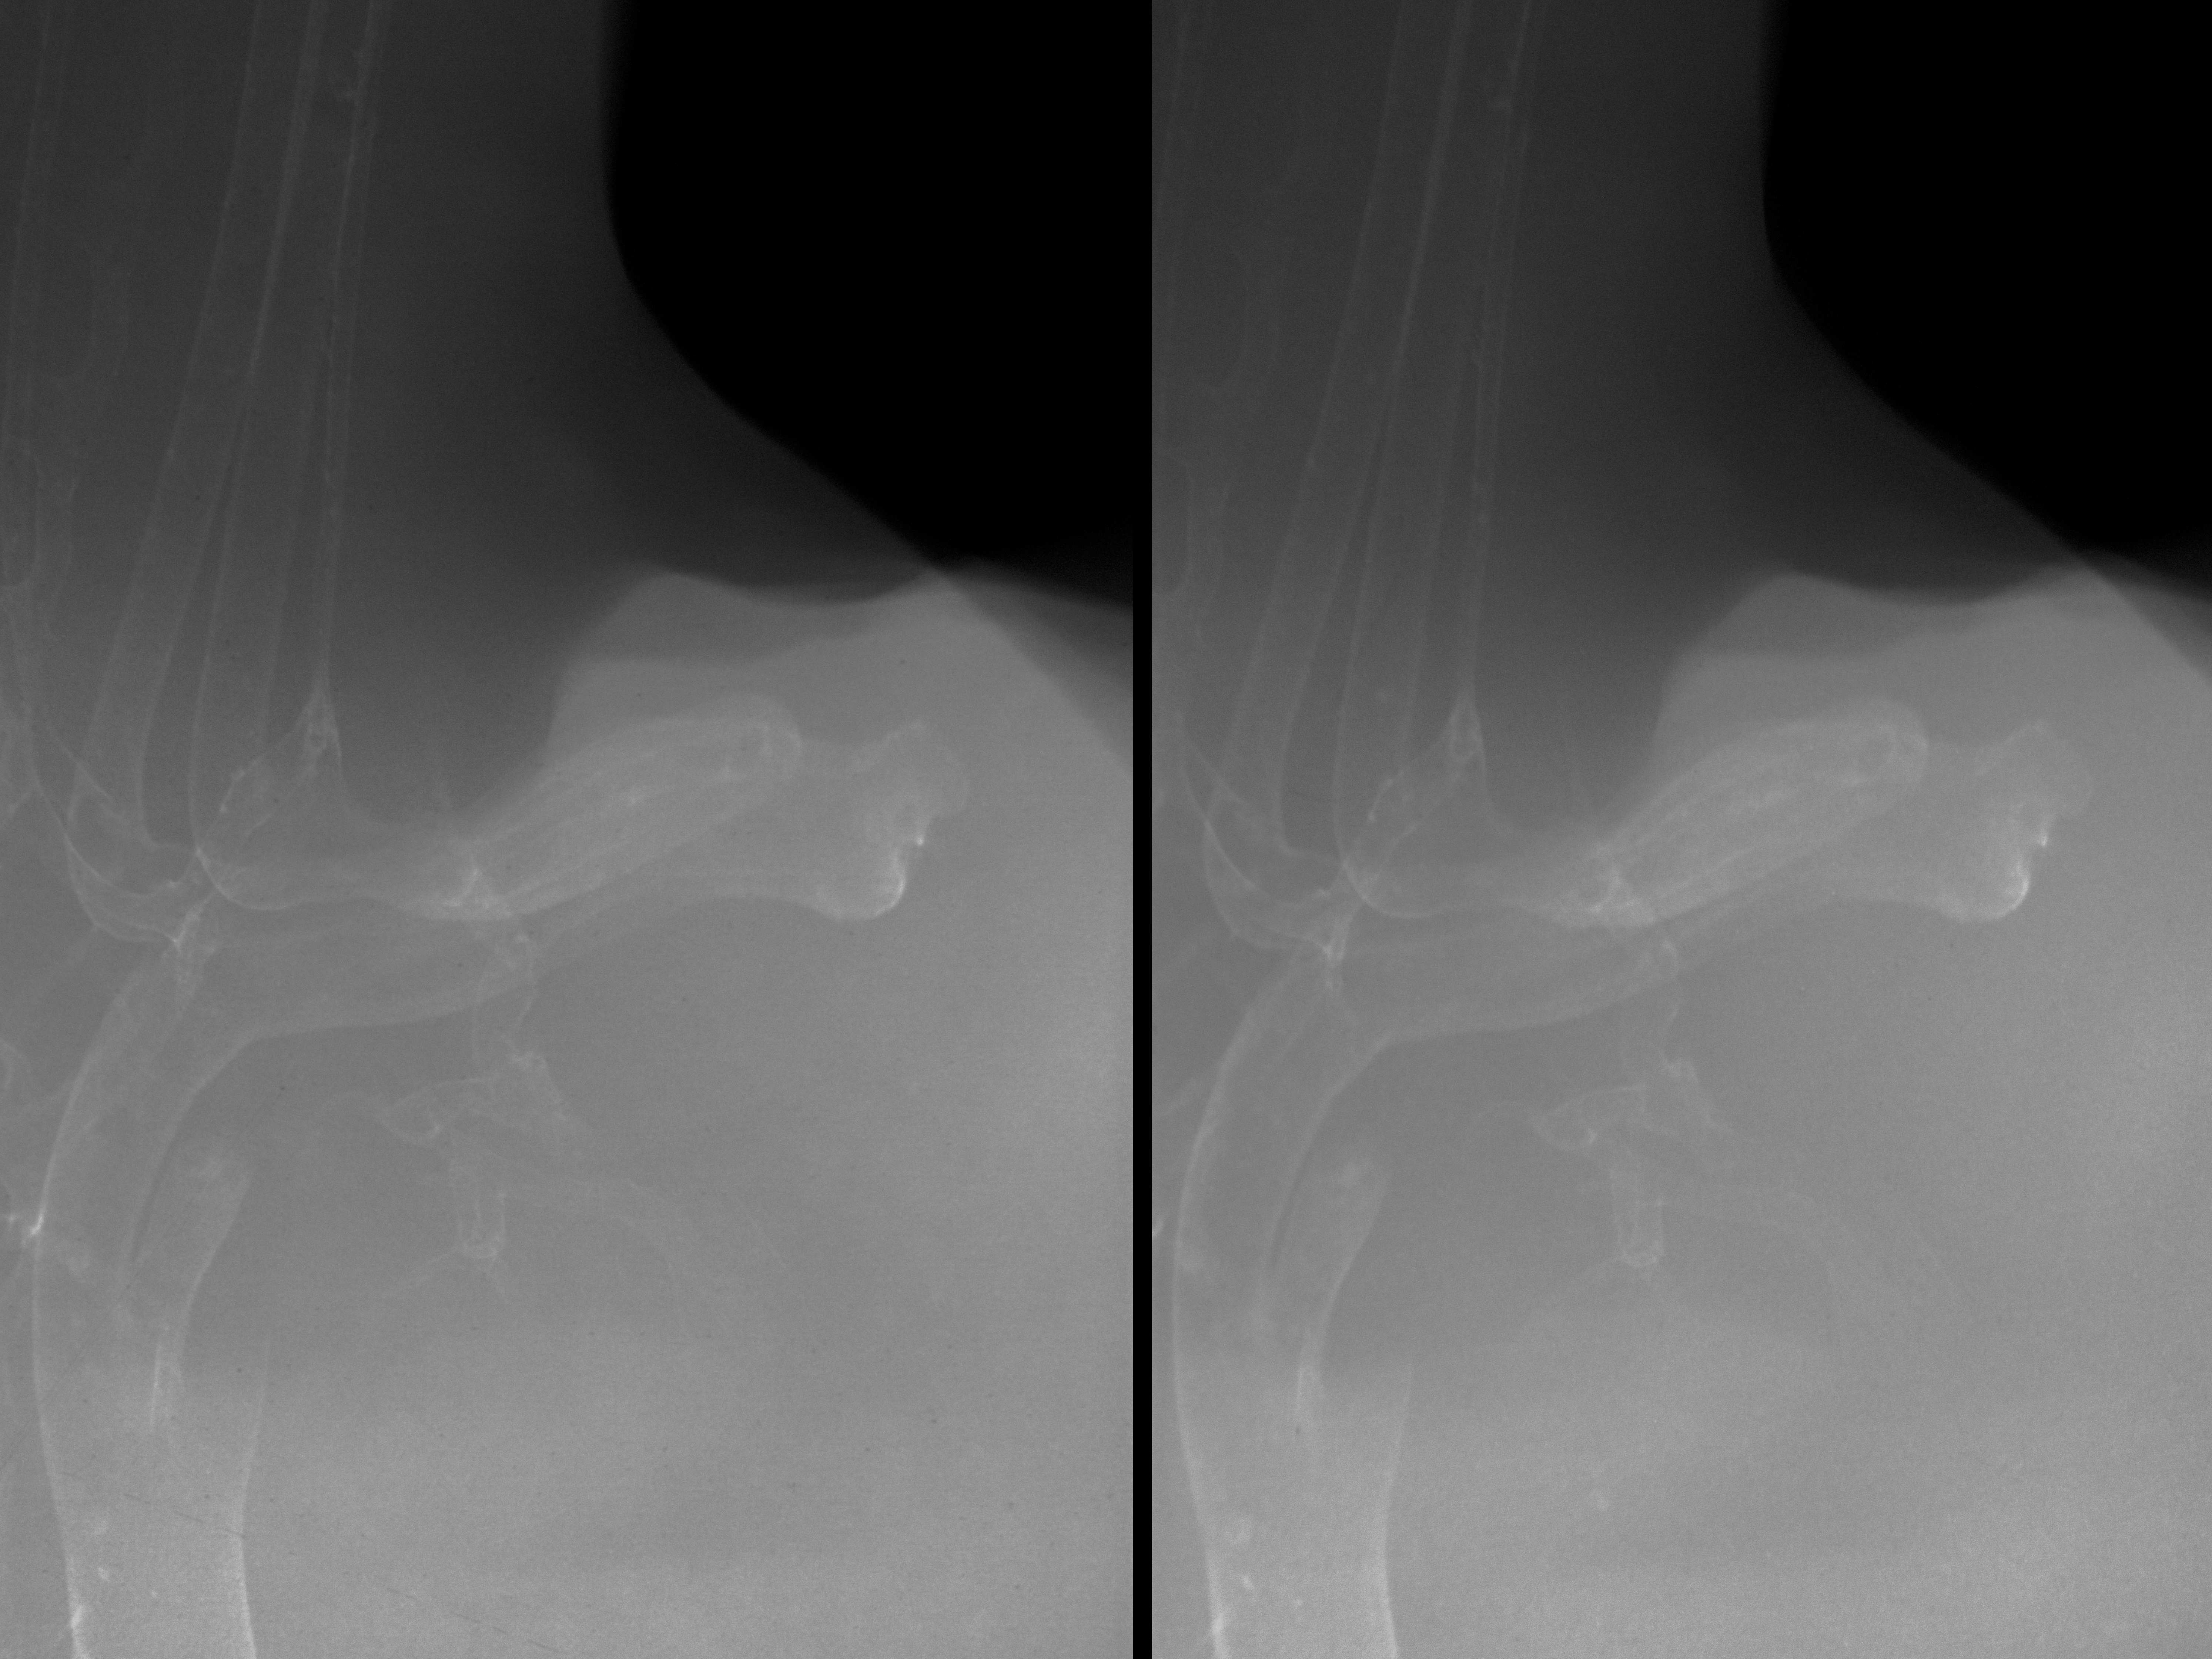

Chick Embryo Microangiography

Hamburger-Hamilton (HH) Stage 31 (approx. 7 days)

Stereo X-Ray Micrographs